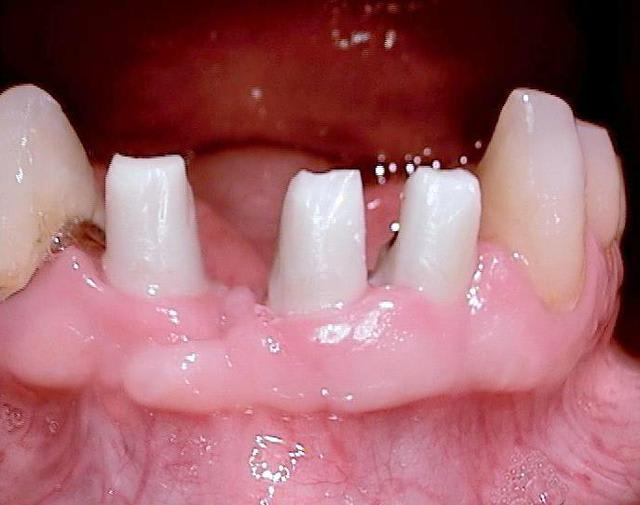

Oui tu as bien raison :-) Ci joint quelques photos en rapport avec ta question ....

c est une bonne question (merci de m avoir expliquer le sens de chiffonne :-) l expression est marrante)

une bonne hygiène est surtout importante si le patient est malade par exemple suite à un "schlaganfall" (en allemand je ne sais pas le terme en francais)

les "vieux" systèmes deux pièces ont un micro espace de 30 micromètres , ce qui explique que les patients devaient nettoyer péniblement ...

en ceramique il n y a pas d accumulation de plaque donc pas de grandes concentration de bactéries gram negatif et anaerobie.La gencive se forme très bien autour de la ceramique ( la nature est le meilleur architecte!)

si après quelques années les couronnes sont retirées, on voit pas d infection....

pour finir c est sur qu il faut quand même se brosser les dents régulièrement. Les patients reviennent juste deux fois par an pour un nettoyage professionnel...